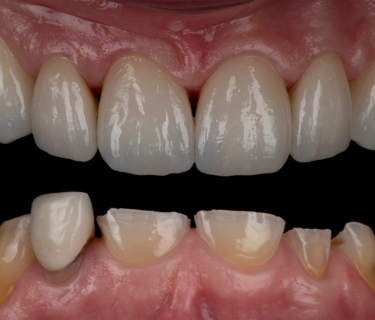

Figure 24: Frontal retracted view – after

Figure 25: Full smile – after

The patient returned after two weeks, and the final restorations were once again assessed. All margins, occlusion and excursions were re-checked and there were no further adjustments necessary (Fig. 24 & 25). Note the beautiful tooth morphology and the detailed surface texture that is achievable with modern digitally designed tooth libraries and state-of-the-art milling machines. The transfer of digital design to final restoration is an exact replication and this can be seen on the comparison of digital overlay against the final zirconia restorations in Figure 26

This patient’s smile is now better balanced, with whiter teeth and more symmetry to the shapes (Fig. 25). The final restorations will require twice yearly review to monitor and assess occlusal stability and function. Over time the posterior support will be re-addressed, and implants again considered.